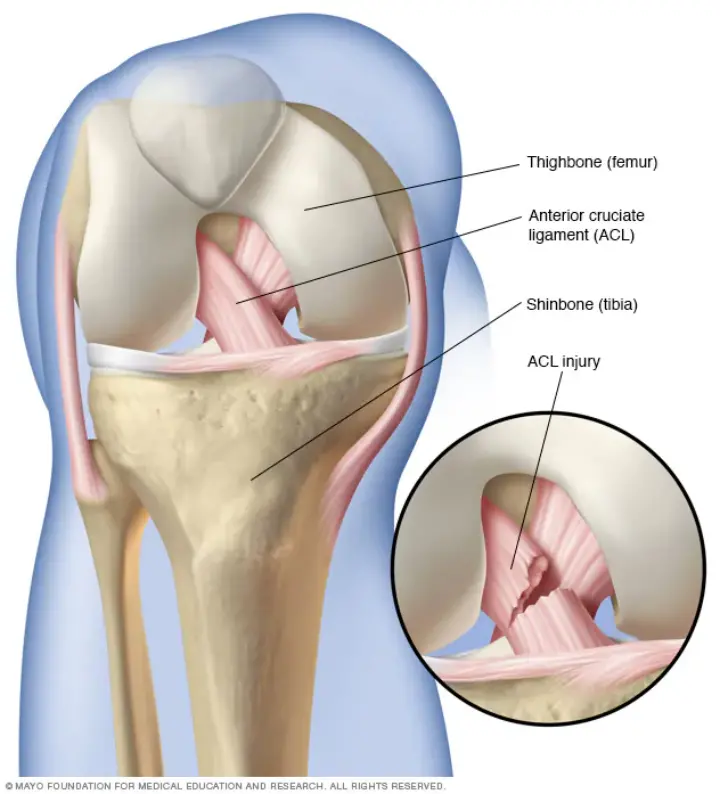

▎前交叉韧带 (ACL) 是稳定膝关节的关键韧带之一。前交叉韧带 (ACL) 连接大腿骨(股骨)和胫骨。

膝关节扭伤是高山滑雪者最常见的损伤,约占成人所有损伤的30%。内侧副韧带(MCL)和ACL损伤(指前交叉韧带的撕裂或扭伤)的发生率相似,分别为18%和16%目前还没有证据表明MCL扭伤的增加与ACL损伤发生率的增加具有相关性。

由于膝关节扭伤现在很常见,最近大多数与损伤预防相关的研究都是针对减少严重的膝关节扭伤。膝关节损伤的机制主要是患者摔倒时膝关节的旋转和外翻。在这种类型的损伤中,滑雪者在抓住他或她的滑雪板内侧边缘时向前摔倒。然后向外旋转,用力外展和向外旋转腿。当滑雪者从跳台着地并伸直膝盖时,靴诱导的前抽屉机制发生,从而导致膝关节ACL损伤。当这种情况发生时,如果一块滑雪板没有及时松开损伤风险增加2倍,如果两块滑雪板都没有松开,那么损伤风险增加会超过3倍。

在滑雪损伤研究中使用的标准描述是受伤次数/滑雪者/天(滑雪天数)。这个数值有局限性,因为它没有考虑到滑雪者每天的实际滑雪量。随着该项运动的发展自20世纪70年代以来,受伤率已从每5-8‰/滑雪日下降至每2-3‰/滑雪日。同时损伤的性质也发生了变化。小腿损伤越来越少见,而膝关节扭伤和上肢损伤的发生率却越来越常见。膝关节损伤的主要部位是前交叉韧带,并且女性发病率是男性的3-6倍。